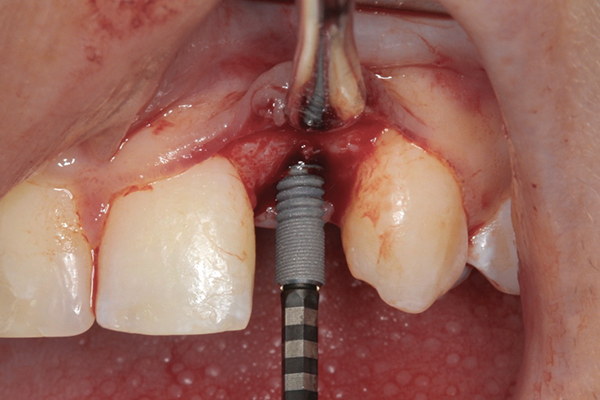

Fig 9 and Fig 10. An implant placed in site No. 10.

When the patient was 18 years old, an implant was placed in site No. 10 with no complications (Figure 9 and Figure 10). Three months later, a periapical radiograph was taken, the implant was torque tested, and a healing abutment (3 mm by 4 mm by 4 mm) was placed.